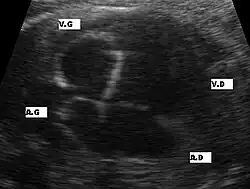

Aspects échographiques avant la naissance

Plusieurs aspects peuvent se rencontrer: une hypertrophie ou une hypoplasie du ventricule gauche ou un ventricule gauche quasiment sans aucune contraction sans aucun flux sanguin au doppler. La circulation du sang étant alors uniquement assuré par le ventricule droit. Le pronostic de cette maladie dépendra du ventricule droit. La visualisation directe d'une ouverture incomplète de la valve aortique et la présence de turbulence au niveau aortique par doppler couleur sont les deux signes directes de cette pathologie mais difficiles à visualiser lors de l'échographie obstétricale. Une brillance anormale du ventricule gauche est un signe de souffrance myocardique par diminution du flux sanguin des coronaires.